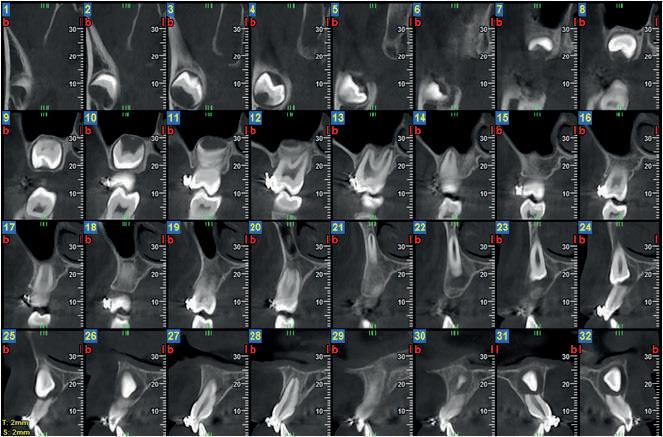

Un elemento dentale si definisce incluso quando il sacco follicolare non si apre in cavità orale in un periodo di tempo di circa 2 anni dopo la fisiologica epoca di eruzione e che ha perso la propria autonoma spinta eruttiva.

Tutti gli elementi dentali possono essere inclusi.

Le sedi generalmente osservabili sono in ordine di frequenza i terzi molari, i canini superiori, i premolari.

Le cause di inclusione possono essere molteplici.

La diagnosi si avvale dell’osservazione clinica e della Diagnostica per immagini che consente di valutare eventuali cause che impediscono la fisiologica eruzione di un elemento dentale.

Il bilancio radiologico 3D fornisce al clinico informazioni utili relative ad ostacoli da rimuovere, all’orientamento del dente, ai rapporti con

strutture limitrofe, alla forma delle radici, a disarmonia dento-maxillofacciale, al rilievo di eventuali anchilosi del dente incluso.

Nel dubbio di anchilosi del dente appare controindicata qualsiasi terapia di disinclusione.

Il canino superiore è il dente che, dopo il terzo molare, ha maggiore probabilità di rimanere incluso, con una incidenza di circa 1% - 5%.

L’inclusione del canino mascellare superiore è più frequente di quella del canino inferiore, con un rapporto di circa 10:1.

È riscontrabile con maggiore frequenza nel sesso femminile con rapporto di 2:1, più frequentemente è monolaterale, nell’8% dei casi è bilaterale.

L’elemento incluso presenta con maggiore frequenza una versione palatale.

La diagnostica per immagini si avvale di tecniche 2D (Ortopanoramica dentale e full endorale) e 3D (3D Cone Beam Computed Tomography - CBCT).

La 3D CBCT consente la perfetta localizzazione, posizione, versione del canino incluso, la valutazione dei rapporti con gli elementi dentali limitrofi ed eventuali contatti di allarme con le strutture anatomiche critiche (seno mascellare, CNP, fossa nasale, forcazione del premolare superiore).

Le notizie fornite al clinico sono necessarie nella pianificazione della terapia di disinclusione, che può essere ortodontica e/o chirurgica.

Nel presente articolo presentiamo 3 casi di inclusione del canino superiore.

Ci riserviamo una futura presentazione di inclusione di canini inferiori.

Fig 2 : stesso Paziente. Ricostruzione panorex.

Il 13 è incluso per ostacolo di eruzione relativo alla presenza di minuti denticoli (odontoma composto).

In emiarcata sinistra, come reperto collaterale, si osserva persistenza di 63 ed agenesia di 23.

Fig 3 - Fig 4 : Paz F. aa 12

Il 13 ed il 23 sono inclusi in posizione alta, mesioangolati, con associate ampie cisti follicolari.

Il 13 è visibile dalla sezione radiale 21 alla 26.

La cuspide di 13 è craniale al 12.

Le cisti follicolari assottigliano, e a destra in parte discontinuano, i tavolati corticali vestibolare e palatale.

Si rileva inoltre rizalisi di 12. 21. 22 relative alla estensione delle lesioni cistiche.

Fig 5 - Fig 6 : Paz F aa 16 Ricostruzione panorex e sezioni radiali dell’emiarcata sinistra.

- Il 23 è in trazione ortodontica per inclusione alta in posizione mesio-trasversa, contiguo al pavimento della fossa nasale sinistra ed al pavimento del seno mascellare sinistro.

L’apice radicolare di 23 si impegna nel pavimento del seno mascellare sinistro; la cuspide erompe in versione vestibolare, craniale all’apice radicolare di 24.